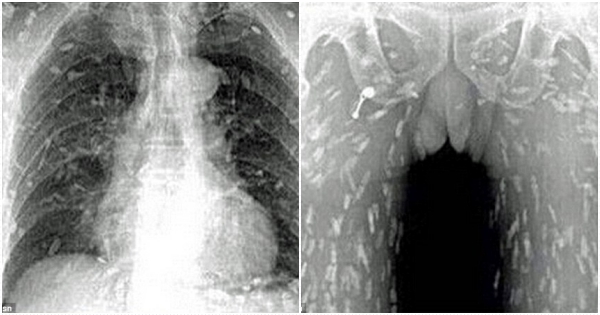

源自日本的生鱼片在世界各地都深受时刻喜爱,由于都是直接生食,其卫生、保鲜等问题显得更加重要。一位来自中国的男性某天忽觉得全身发痒而来到医院做检查,拍了X光片后,医生发现…